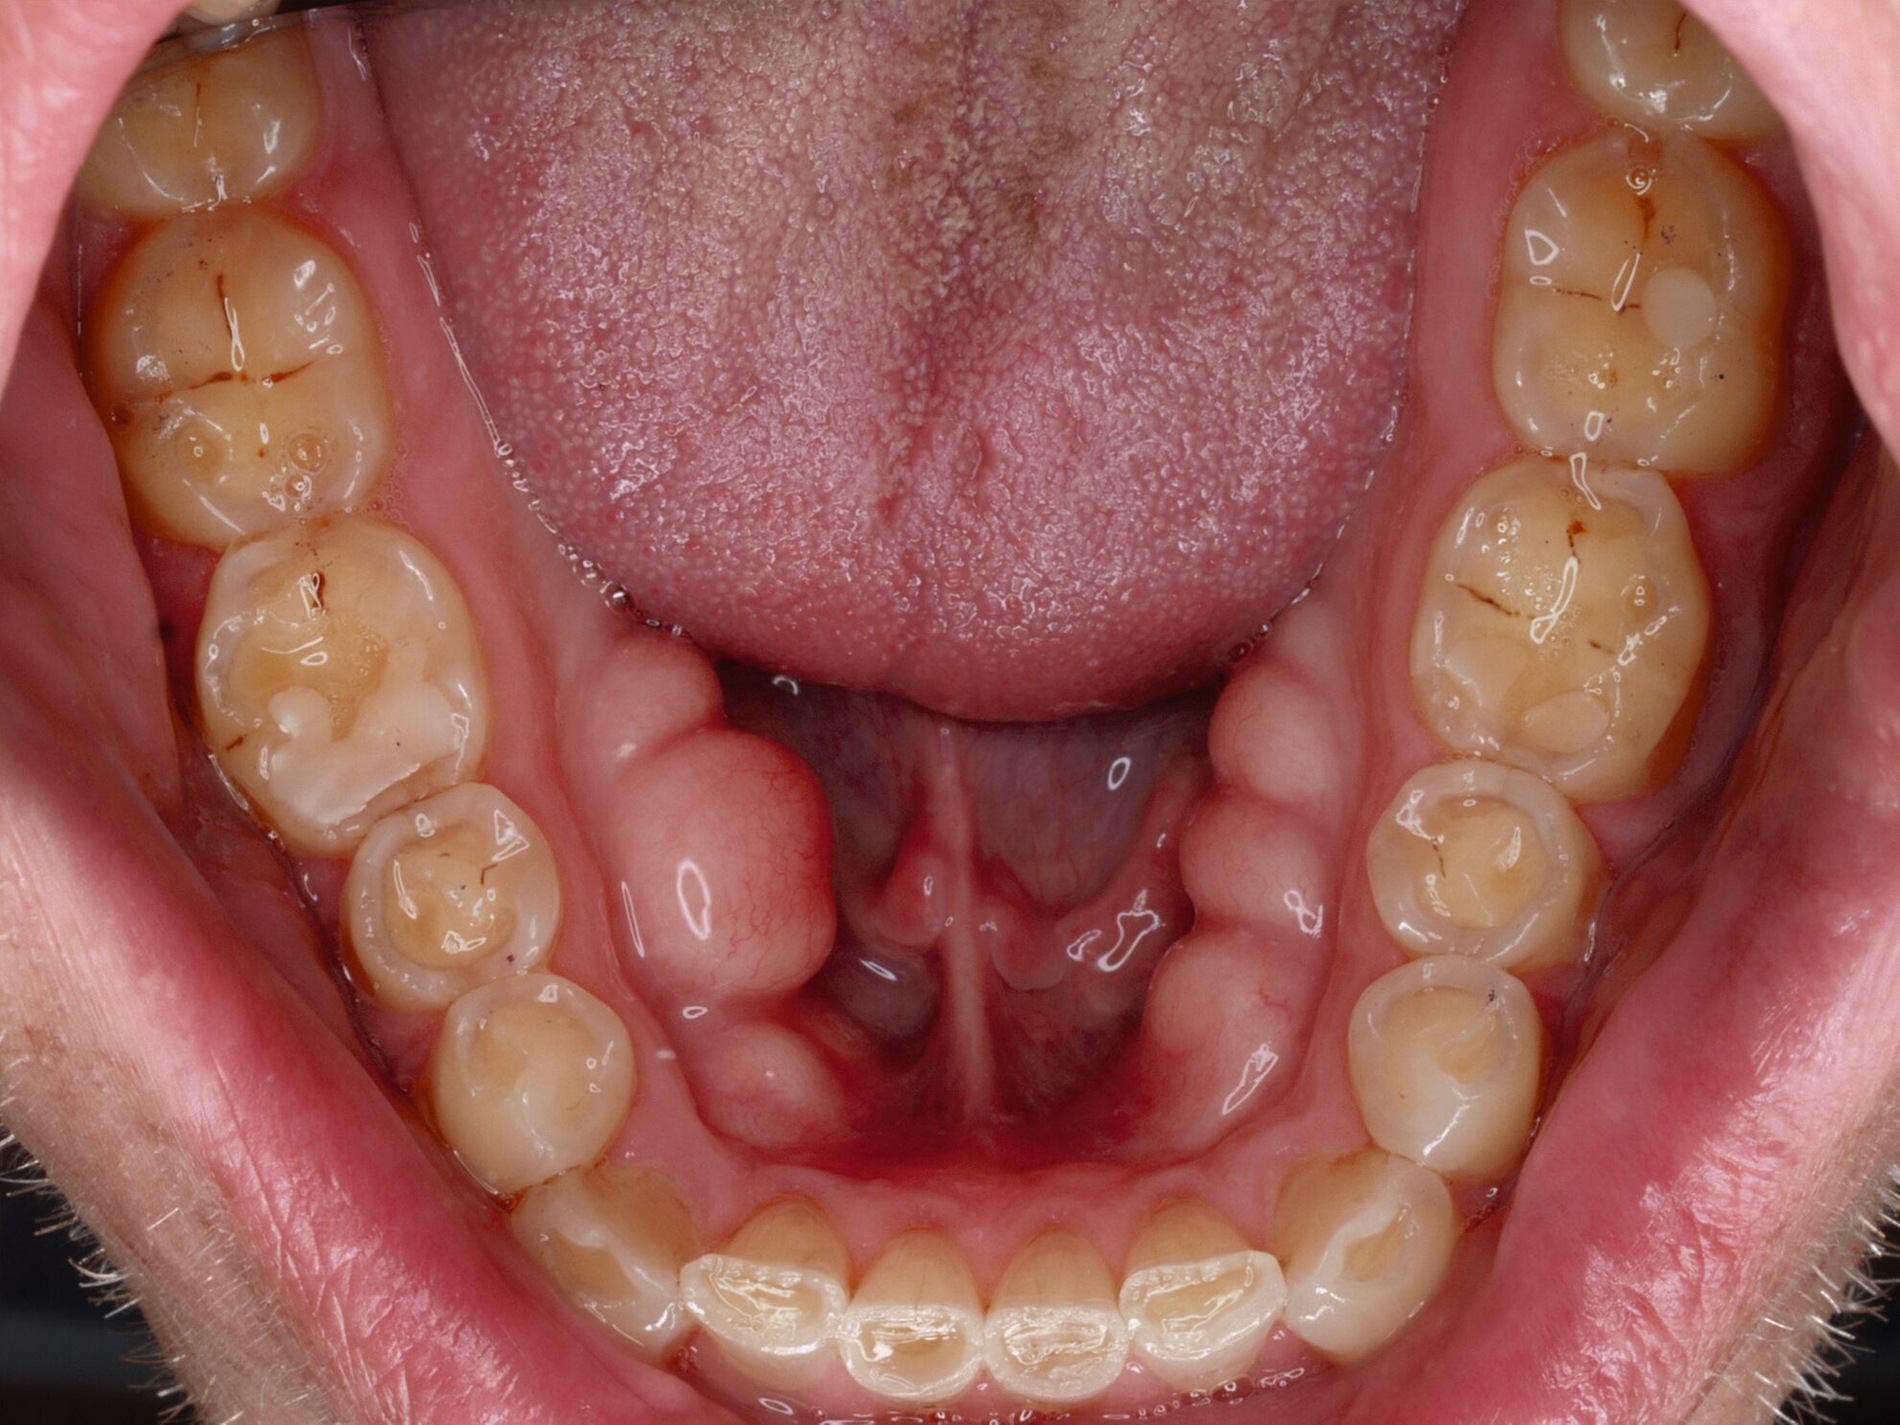

Das unter Beteiligung des Autors entwickelte Tooth Wear Evaluation System (TWES) 2.0 [Wetselaar et al., 2020] identifiziert per Screening Patienten mit erhöhten Verschleißwerten, vergleichbar mit dem PSI in der Parodontologie oder dem CMD-Kurzbefund. Bei auffälligen Werten folgt ein differenzierter Zahnverschleiß-Status einschließlich der Erfassung oraler und vestibulärer Substanzverluste [Wetselaar et al., 2016 sowie von Pathologie-Symptomen und einer strukturierten Diagnose [Tonetti und Sanz, 2019; Wetselaar, 2020]. Den Einsatz in der Praxis illustriert der in den Abbildungen beschriebene Patientenfall aus dem CMD-Centrum Hamburg-Eppendorf.

Im Beispiel ist daher die Diagnose ein generalisierter erheblicher und lokalisierter moderater pathologischer Zahnverschleiß überwiegend mechanischer und zudem chemischer Ursache. Die sich daraus ableitende Erkenntnis ist, dass in allen Sextanten Zähne freiliegende Dentinkerne aufweisen (generalisierter moderater Zahnverschleiß), dass darüber hinaus Zähne erheblich geschädigt und somit gefährdet sind, dass Merkmale eines pathologischen Geschehens bestehen – und dass als Ursache neben dem dominierenden Bruxismus ein Säureeinfluss hinzukommt.

Auch wenn Restaurationen nach Möglichkeit vermieden werden sollten, ist deren Verfügbarkeit für die Betroffenen individuell höchst wichtig, weil sie bestehende Schmerzen beseitigt, die verlorengegangene Kauleistung wiederherstellt und ästhetische und nicht zuletzt auch phonetische Einschränkungen aufhebt. Bei dem in den Abbildungen beschriebenen Fall korrelierte der erhebliche Zahnverschleiß mit der Lokalisation der Zahnschmerzen des Patienten. Direkte Restaurationen mit Kompositen hatten keinen Bestand. Die durchgeführte restaurative Behandlung hingegen hat Bestand, die Schmerzen waren danach umgehend verschwunden und sind seit zehn Jahren nicht wiedergekehrt.

Dabei führt die Verfügbarkeit hochfester Dentalkeramiken heute zu viel weniger invasiven Restaurationen als früher durchgängig übliche metallkeramische Kronen, und die Transluzenz der keramischen Werkstoffe ermöglicht zudem natürlichere Restaurationen. Der beschriebene Behandlungsfall zeigt, wie eine mehrstufige Zahnverschleiß-Diagnostik im Praxisalltag umgesetzt wird, mit initialem Zahnverschleiß-Screening und einer im Bedarfsfall erfolgenden erweiterten Diagnostik per Zahnverschleiß-Status.